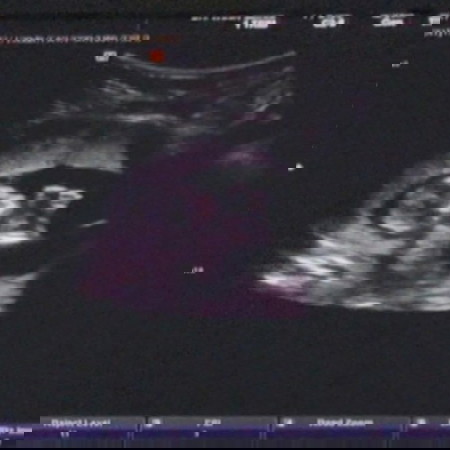

13w ค่ะ กำหนดคลอด12/12/21 แม่บ้านไหนกำหนดคลอดเดือนธันวาคมบ้างคะ มาแชร์ ภาพอัลตร้าซาวด์กันหน่อย ท้องแรกค่ะ คุณแม่เห่อลูก

บ้านนี้ 30 ธันวาค่ะ 😊✌️